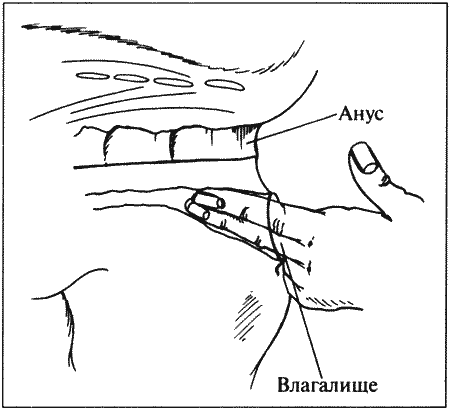

При обследовании репродуктивного тракта рекомендуется проводить:

• в случае предполагаемого эструса выявление признаков поведенческого эструса (отведение хвоста, поднятие крупа), которое можно осуществить поглаживанием перианальной области;

• исследование влагалища у сук методом пальпации и с применением эндоскопа (у кошек подобное исследование затруднительно, см. раздел Методы диагностики, вагиноскопия);